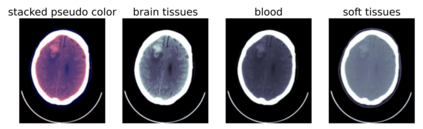

We present an effective method for Intracranial Hemorrhage Detection (IHD) which exceeds the performance of the winner solution in RSNA-IHD competition (2019). Meanwhile, our model only takes quarter parameters and ten percent FLOPs compared to the winner's solution. The IHD task needs to predict the hemorrhage category of each slice for the input brain CT. We review the top-5 solutions for the IHD competition held by the Radiological Society of North America(RSNA) in 2019. Nearly all the top solutions rely on 2D convolutional networks and sequential models (Bidirectional GRU or LSTM) to extract intra-slice and inter-slice features, respectively. All the top solutions enhance the performance by leveraging the model ensemble, and the model number varies from 7 to 31. In the past years, since much progress has been made in the computer vision regime especially Transformer-based models, we introduce the Transformer-based techniques to extract the features in both intra-slice and inter-slice views for IHD tasks. Additionally, a semi-supervised method is embedded into our workflow to further improve the performance. The code is available in the manuscript.